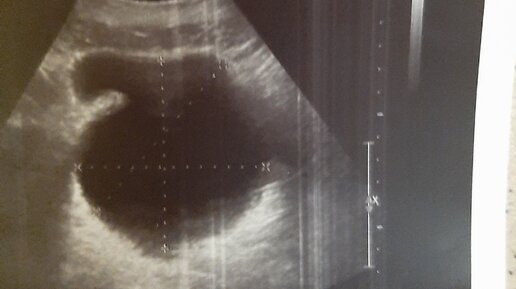

УЗИ мочевого пузыря. Зачем нужно пить перед исследованием? Что пить? Как это сделать правильно?

В наше время современные методики исследования позволяют осматривать пациента с минимальной подготовкой: Мы больше не требуем делать клизму перед УЗИ простаты и приходить женщинам на гинекологическое УЗИ с полным мочевым пузырем (это желательно, но не обязательно)...